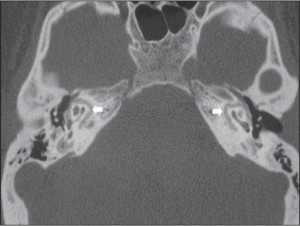

Компьютерная томография височных костей высокого разрешения (КТ) — это высокоинформативный объективный метод диагностики отосклероза. КТ позволяет точно визуализировать структуры височных костей, выявлять расположение, распространённость очагов и активность отосклероза. Также можно выявить очаги как пониженной, так и повышенной плотности.

КТ-сканирование играет важную роль при диагностике перед кохлеарной имплантацией: позволяет оценить состояние связочного аппарата и слуховых косточек, определить объём, тактику и прогноз операции. Диагностическая чувствительность КТ височных костей составляет 80–95 % [3] .

Конусно-лучевая КТ височных костей — инновационная технология, которую проводят с помощью тонкого прерывистого конического пучка рентгеновского излучения. Конусно-лучевая КТ отличается от мультиспиральной КТ по форме рентгеновского луча. При конусно-лучевой КТ ниже лучевая нагрузка, цена исследования также ниже, при этом чувствительность метода составляет 100 %. Аппараты КЛКТ есть в государственных и частных медицинских учреждениях.

Как диагностируется отосклероз? Диагноз отосклероза ставится на основании комплексного анализа жалоб, аудиометрической картины, вестибулярных и других вспомогательных тестов, а также компьютерной томографии. При подозрении на отосклероз нужно обязательно сделать КТ височной кости.

Компьютерная томография (КТ) при отосклерозе выявляет типичные изменения в пирамиде височной кости и в типичных случаях подтверждает этот диагноз почти со стопроцентной уверенностью. Поэтому при подозрении на отосклероз нужно обязательно проходить КТ, но при условии, что врач, анализирующий снимки, хорошо разбирается в проблеме.

Типичные признаки начальной, фенестральной формы отосклероза на КТ – это участок понижения плотности, как правило округлой или неправильной формы, расположенный в костной капсуле лабиринта у переднего края окна преддверия. При развитии болезни этот очаг увеличивается и вовлекает передние отделы основания стремени. При улитковой форме аналогичные очаги располагаются вокруг улитки.

КТ височной кости при фенестральной форме отосклероза. Визуализируется очаг пониженной плотности (отоспонгиоз) у переднего края окна преддверия.

КТ при улитковой (кохлеарной) форме отосклероза. Участки понижения плотности, окружающие базальный завиток улитки.